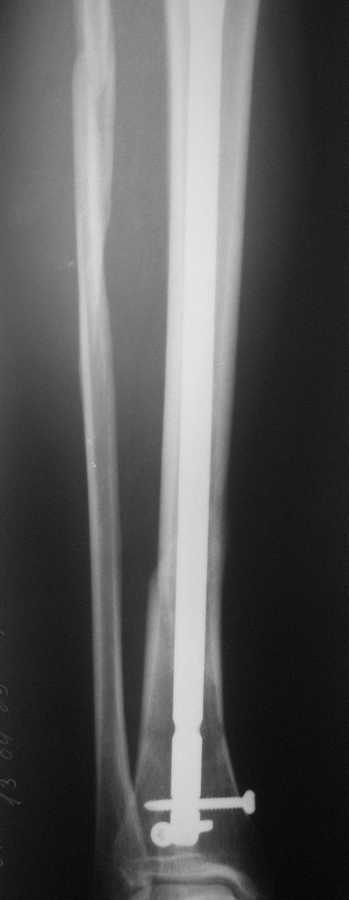

БИОС голени. В чем ошибка? |

В январе 2009 года нами оперирована пациентка с переломом н\3 голени штифтом Expert. Динамизация через 4 месяца, пациентка при этом уже ходила с тростью. Дома периодически передвигалась без дополнительной опоры.

В настоящее время - через 9 месяцев с момента операции периодически в вечернее время беспокоят ноющие боли в места перелома (не постоянно). При беседе выяснено, что боли чаще беспокоят после того, как днем она походит по дому без трости. Пальпаторно по гребню берцовой кости болей нет, но по задне-внутренней поверхности б\б кости пальпирутеся западение на уровне места перелома.

В чем ошибка??? и что делать???